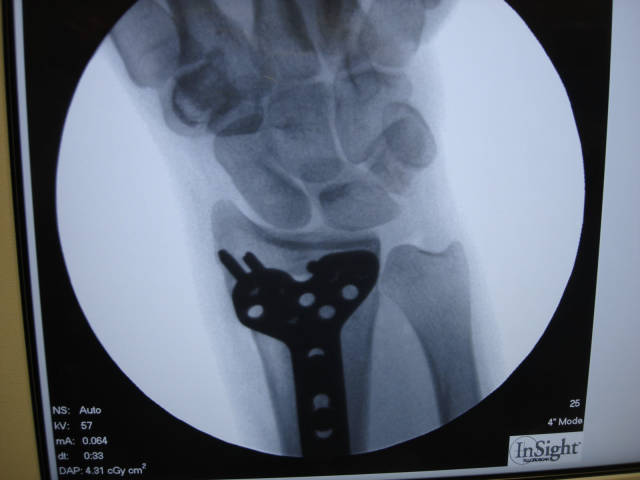

9. 术中 X 线影像证实,骨折最终获得解剖复位,钢板螺钉的位置满意:

钢板的位置非常重要,因为钢板不仅可以支撑骨折块,适当的位置还可以避免远端锁定螺钉侵入桡腕关节。术中仔细拍摄 X 线影像,投照方向与桡骨远端的掌倾角一致,可准确地观察桡骨远端桡侧的关节面,而术中先置入尺侧的螺钉也可更准确地观察桡侧的关节面。

螺钉穿透背侧皮质有激惹伸肌腱导致肌腱断裂的风险。锁定螺钉的性能与普通螺钉不同,没必要将螺钉穿透背侧皮质。